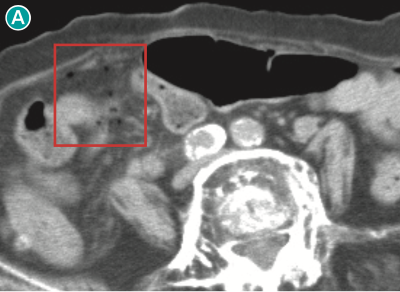

図 nonsurgical pneumoperitoneumの一例(単純CT,脂肪条件)

90歳代女性で発熱を主訴に来院.下腹部レベル(🅐)では,腸間膜を主体に複数の小さな腹腔内free air が認められる( ).骨盤部レベル(🅑,🅒)では,子宮( ![]() )および膣(

)および膣( ![]() )の腔内にもairが認められる.本例は消化管穿孔はなく,女性生殖器の感染により生じたairが腹腔内に移動したものと考えられた.

)の腔内にもairが認められる.本例は消化管穿孔はなく,女性生殖器の感染により生じたairが腹腔内に移動したものと考えられた.